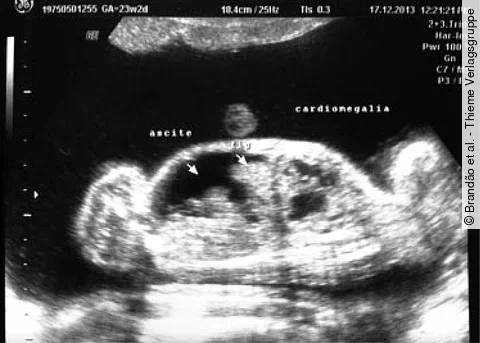

Eine 38-jährige Frau ist nach spontaner Empfängnis schwanger mit monochorioten, diamnioten Zwillingen. Ihre Krankengeschichte umfasst eine Wirbelsäulenentzündung und Tagesschläfrigkeit.